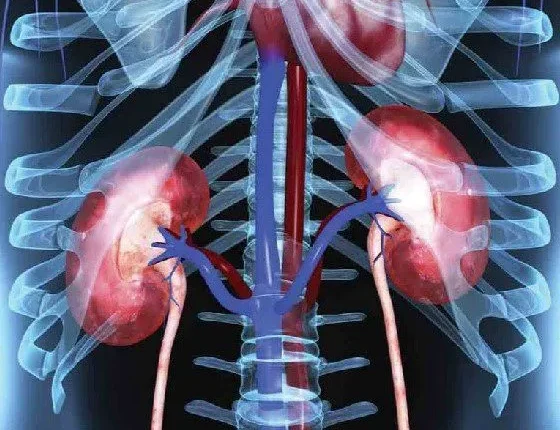

Η νεφρική νόσος προσβάλλει εκατομμύρια ανθρώπους κάθε χρόνο, ωστόσο είναι λίγα τα σημάδια ή τα συμπτώματα που υποδηλώνουν την εμφάνισή της.

Υπάρχουν έξι προειδοποιητικά σημάδια για τη νεφρική νόσο, συμπεριλαμβανομένης της υψηλής πίεσης του αίματος. Τα άλλα πέντε είναι το αίμα ή η πρωτεΐνη στα ούρα και τα μη φυσιολογικά αποτελέσματα των εργαστηριακών εξετάσεων, όπως η υψηλή κρεατινίνη ή το άζωτο ουρίας στο αίμα και το χαμηλό ποσοστό σπειραματικής διήθησης. Αυτά τα συμπτώματα μπορεί να σημαίνουν ότι οι νεφροί έχουν υποστεί βλάβη και δεν λειτουργούν πλέον σωστά, ώστε να μπορούν να απομακρύνουν τα απόβλητα από το σώμα και να διατηρούν την υγεία.

Η πρώιμη νεφρική νόσος σπανίως προκαλεί συμπτώματα. Ωστόσο, τα συμπτώματα που μπορεί να αναπτυχθούν, καθώς η νόσος εξελίσσεται, συχνά αποδεικνύονται ασαφή και έτσι υπάρχει ο κίνδυνος να αγνοηθούν ή κάποιος να τα μπερδέψει με άλλες συνθήκες. Ενα άτομο μπορεί να αισθάνεται πιο κουρασμένο απ’ ό,τι συνήθως ή να δυσκολεύεται να συγκεντρωθεί. Συχνά έχει μειωμένη όρεξη και ξηρό δέρμα με φαγούρα. Οι διαταραχές του ύπνου μπορεί να περιλαμβάνουν νυχτερινές κράμπες των μυών.

Η νεφρική νόσος είναι μια προοδευτική νόσος και μπορεί να οδηγήσει σε νεφρική ανεπάρκεια. Πρόκειται για μια απειλητική κατάσταση για τη ζωή του ανθρώπου και απαιτεί θεραπεία για να παραμείνει κάποιος εν ζωή με αιμοκάθαρση για τον καθαρισμό του αίματος ή μεταμόσχευση για την αντικατάσταση του κατεστραμμένου οργάνου. Η νεφρική νόσος προκαλεί, επίσης, βλάβες σε άλλα όργανα όπως η καρδιά. Επομένως, όσο νωρίτερα ανακαλύψει κάποιος ότι πάσχει από νεφρική νόσο και ξεκινήσει τις θεραπείες, τόσο πιο εύκολο είναι να προλάβει τις όποιες επιπλοκές.